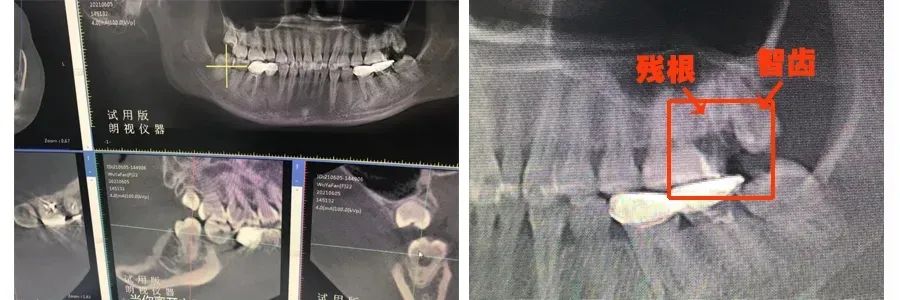

▲患者的牙片

根据患者的牙片,我们可以得出如下结论:

1、那颗烂掉的大牙因为之前做过治疗,长期有炎症,跟周围的骨头存在粘连的可能性;

2、需要治疗的位置正好挨着上颌窦,有一定的治疗风险。

这恐怕也是牙科诊所不敢轻易处理的原因。